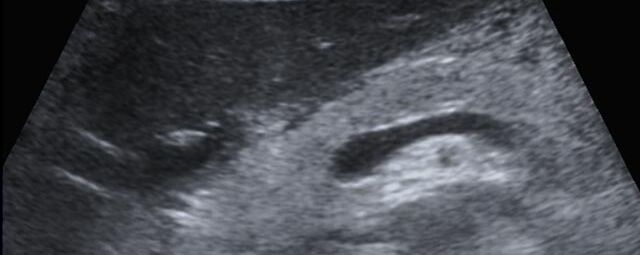

Die Sonographie ist ein bildgebendes Verfahren in der medizinischen Diagnostik, das mit Ultraschallwellen arbeitet. Ultraschall ist Schall mit einer Frequenz oberhalb der menschlichen Hörgrenze. Im medizinischen Bereich werden je nach Körperregion Ultraschallwellen in einem Frequenzbereich von ca. 3,5 – 18 Mhz verwendet. Die körpernahe Ultraschallsonde sendet durch einen piezoelektrischen Effekt kurze Schallwellenimpulse in den Körper. Ultraschall-Gel stellt den Kontakt zwischen Sonde und Körper her. Je nach Gewebeart werden diese Schallwellen im Körper unterschiedlich stark reflektiert. Anhand des zurückgesendeten Schallmusters kann das Ultraschallgerät Schnittbilder berechnen, auf denen die Organe des Körpers nach krankhaften Veränderungen untersucht werden können.

Der Arzt bewegt den Schallkopf mit leichtem Druck in verschiedene Richtungen. Die zu untersuchenden Strukturen können somit aus verschiedenen Perspektiven betrachtet werden. Aussagekräftige Bilder werden festgehalten und digital archiviert, Strukturen oder Organe können zusätzlich vermessen werden. Ein kurzes Befundgespräch erfolgt direkt nach der Untersuchung. Ihr zuweisender Arzt erhält von uns schriftlich einen ausführlichen Befundbericht.